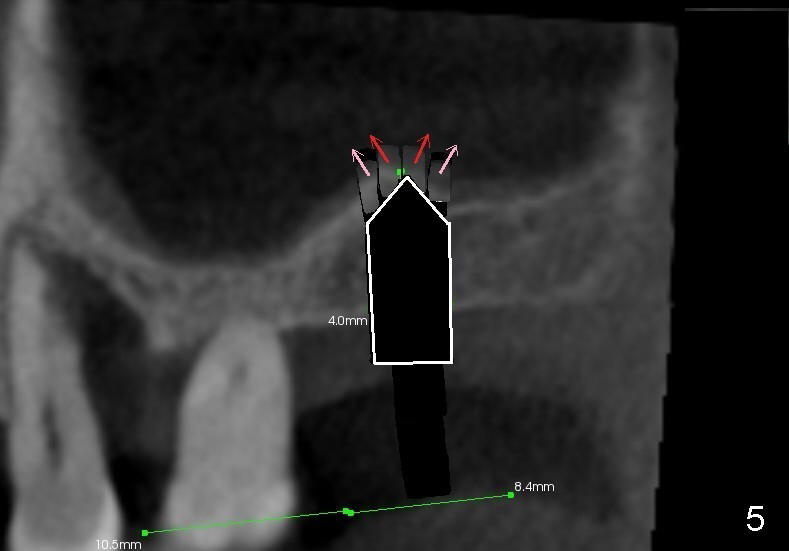

As the diameter of osteotomes increases (from 2, 3 to 4 mm), more of sinus

floor undergoes green stick fracture (Fig.5 pink arrows). At the same

time, more bone is brought apically (not shown). Finally a tapered

osteotome with flat end or tap is used to further lift the sinus floor (Fig.6

white arrow). This time the fractured bone fragments (red and pink arrows)

are more or less at the same level.

The apical end of the ensuing implant

should be covered by vascularized (attached to the sinus membrane) bone

fragments.